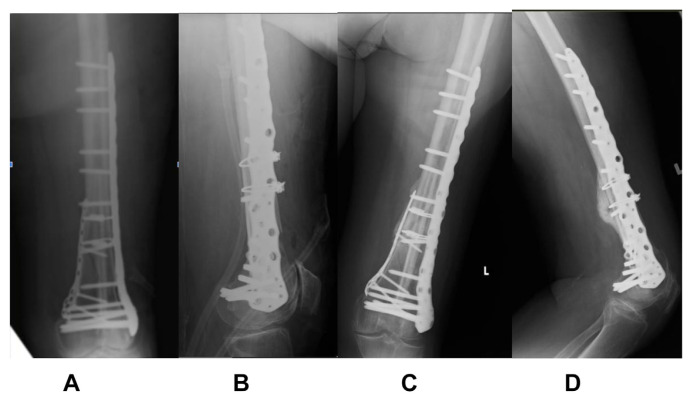

Introduction: Distal femur fractures result in high morbidity and mortality - comparable to that of hip fractures. The commonly used surgical fixation techniques today, locked plating and intramedullary nailing, have shown high postoperative complication rates. Thus, many surgeons temporarily keep patients non-weight bearing in the early postoperative stage. Increased time to ambulation after surgery is known to increase systemic complications in patients. We aim to investigate if an augmented fixation technique involving the use of a fibular strut allograft with dual locking plates helps to allow early mobilization postoperatively without adverse outcomes.

Methods: Five geriatric patients (four female, one male) with distal femur fractures (native or periprosthetic) were treated in our institution with the aforementioned technique, and were allowed early postoperative weight-bearing. These patients were followed up for postoperative outcomes. The primary outcomes studied were non union, implant failure and wound complications. Secondary outcomes studied include time to union, and Sander's functional score.

Results: There were no cases of non-union, implant failure or wound related infection. All patients achieved radiological union (mean = 12.6 weeks). Using Sander's functional scoring, two patients achieved excellent, two achieved good and one had fair outcomes. All patients were followed up for at least 6 months after operation.

Conclusion: Our method of augmented fixation with fibular strut allografts potentially allows for early weight bearing without adverse outcomes. Further studies with larger sample sizes are required to validate our findings.